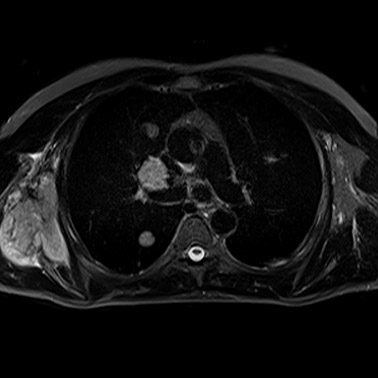

MRT bei Krebserkrankungen (Onkologie)

Die Magnetresonanztomographie (MRT) nimmt bei der Diagnose, dem Staging und der Verlaufskontrolle von onkologischen Erkrankungen einen wichtigen Platz ein.

Auf makroskopischer Ebene lassen sich mit MRT genaue morphologische Informationen (Größe, Form) sowie die Lage der meisten Weichteiltumoren bestimmen. Morphologie und Lage des den Tumor umgebenden, nichtbefallenen Weichteilgewebes sind von lebenswichtiger Bedeutung und bestimmen das Vorgehen bei einer nachfolgenden Strahlentherapie.

Leber- und Knochenmetastasen

bei Brustkrebs